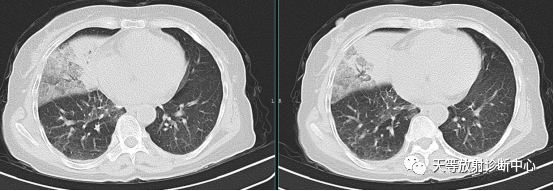

上图注:来源《肺部CT精解》.原著 Kyung Soo Lee.Joungho Han. Man Pyo Chung.Yeon Joo Jeong.主审:许乙凯.王贵生.主译:吴元魁.蔡开灿。

▲上图2021.-7.20检查右肺中叶大叶性肺炎,病灶大片实变影,内部支气管充气征,支气管充气征主要由支气管周围肺组织氧气含量降低、密度升高造成。

▲同上病例:经过治疗后,2020.8.6复查,肺内病变吸收减少,实变影中更多的支气管充气征。